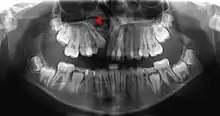

![]() Human jaws with anterior (frontal) portion of alveolar processes cut away towards right | |